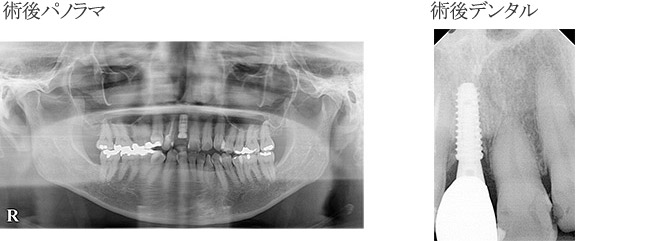

з—ҮдҫӢ3

дёҠйЎҺе·ҰеҒҙпј“з•ӘгҒ®жӯҜж №з ҙжҠҳгҒ«гҒЁгӮӮгҒӘгҒҶз–јз—ӣзҷәз”ҹгҒ®гҒҹгӮҒжқҘйҷў

| в‘ жІ»зҷӮеҗҚ | жӯҜгҒ®з ҙжҠҳгҒ«гӮҲгӮҠжӯҜеҶ дҝ®еҫ© |

|---|---|

| в‘ЎиІ»з”Ё | гӮёгғ«гӮігғӢгӮўгҒ«гӮҲгӮӢеүҚжӯҜдҝ®еҫ©пјҲгӮөгғјгӮёгӮ«гғ«гӮ¬гӮӨгғүдҪҝз”Ёпјүпј“пј•дёҮеҶҶ/жң¬ |

| в‘ўжңҹй–“ | жҠңжӯҜеҫҢ1гҒӢжңҲеҫҢгҖҖеҫ…жҷӮеҹӢе…ҘгҖӮпј“гҒӢжңҲеҫҢи©ҰйҒ©гҖҒпј’йҖұй–“еҫҢгӮёгғ«гӮігғӢгӮўгӮ»гғғгғҲ |

| в‘ЈйҖҡйҷўй »еәҰ | гӮӘгғҡзҝҢж—ҘгҒ«жҙ—жө„гҖҒпј‘йҖұй–“еҫҢиҰіеҜҹгҖҒгҒ•гӮүгҒ«пј‘йҖұй–“еҫҢжҡ«й–“зҫ©жӯҜгҒ®зўәиӘҚгҖӮпј‘гҒӢжңҲжҜҺгҒ«зўәиӘҚгҖӮпј“гҒӢжңҲеҫҢпј©пјіпјұгҒ«гҒҰгӮӘгӮ№гғҶгӮӘгӮӨгғігғҶгӮ°гғ¬гғјгӮ·гғ§гғігҒ®зўәиӘҚгҖҒгӮ·гғӘгӮігғіеҚ°иұЎгҖҒи©ҰйҒ©еҫҢжң¬гӮ»гғғгғҲгҖӮ |

| в‘ӨжӮЈиҖ… | пј–пј“жӯігҖҖеҘіжҖ§ |

| в‘ҘжІ»зҷӮеҶ…е®№ | дёӢйЎҺиҮјжӯҜйғЁж¬ жҗҚгҒ®гҒҹгӮҒеүҚжӯҜгҒ§гҒӢгӮҖгҒ“гҒЁгҒҢеӨҡгҒҸгӮ¬гӮӨгғүгӮ’гҒҷгӮӢзҠ¬жӯҜгҒҢе’¬еҗҲеҠӣгҒ§еҫҗгҖ…гҒ«ејұгӮҠз ҙжҠҳгҒ—гҒҹгӮӮгҒ®гҒЁиҖғгҒҲгӮүгӮҢгӮӢгҖӮ |

| в‘ҰжІ»зҷӮзөҗжһң | еҜ©зҫҺзҡ„гҒ«гӮӮж©ҹиғҪзҡ„гҒ«гӮӮжӮЈиҖ…гҒ•гӮ“гҒҢжәҖи¶ігҒ§гҒҚгӮӢзөҗжһңгҒЁгҒӘгӮҠе®ҡжңҹжӨңиЁәгӮ’гҒҠйЎҳгҒ„гҒ—гҒҰгҒ„гӮӢгҖӮгҒҹгҒ еҸҚеҜҫеҒҙгҒ®пј“з•ӘгҒ®з ҙжҠҳгҒҢгҒҠгҒҚгҒӘгҒ„гҒӢеҝғй…ҚгҒ§гҒӮгӮӢгҒЁгӮӮжӮЈиҖ…гҒ•гӮ“гҒ«гӮӮи©ұгҒ—гҒҰгҒ„гӮӢгҖӮ |

| ⑧注ж„ҸзӮ№ | гӮ„гҒҜгӮҠдёӢйЎҺгҒ®иҮјжӯҜйғЁгҒҫгҒ§е…ҘгӮүгҒӘгҒ„гҒЁй•·жңҹе®үе®ҡгҒҢжңҹеҫ…гҒ§гҒҚгӮӢгҒЁгҒҜиЁҖгҒҲгҒӘгҒ„гҒҢдәҲз®—дёҠгҒ®гҒ“гҒЁгӮӮгҒӮгӮҠгҒ—гҒЈгҒӢгӮҠдёӢйЎҺгҒ®йғЁеҲҶеәҠзҫ©жӯҜгҒ®иЈ…зқҖгӮ’гҒҠйЎҳгҒ„гҒ—гҒҰгҒ„гӮӢгҖӮ |